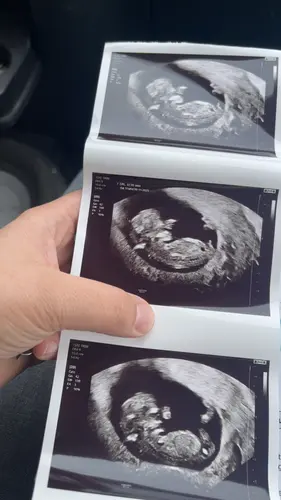

Iemand die een gokje wil doen? Hier was ik 11 weken

Ik zie m

Hier nog niet